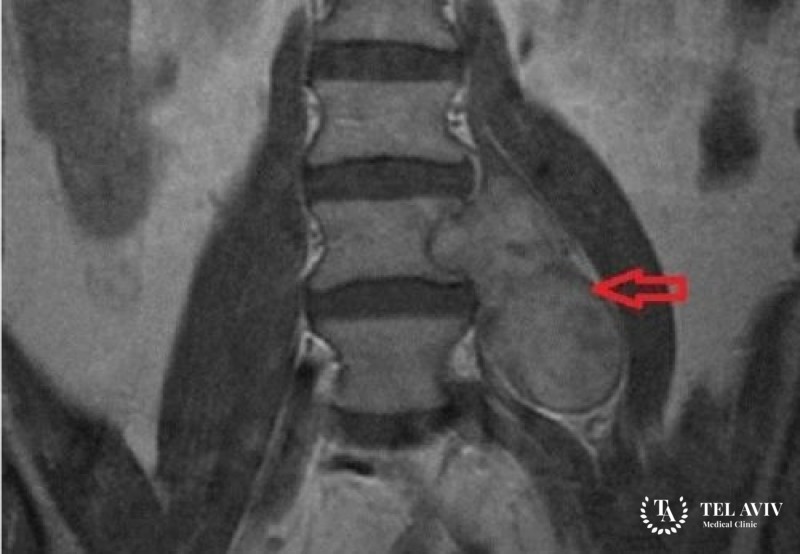

Невриномы в области спинного мозга, хребта, относят к классу доброкачественных новообразований. Болезнь отличается высоким уровнем распространенности. Она начинает развиваться в спинномозговых корешках. Отличаются невриномы медленным увеличением в размерах. Опасность опухоли заключается в высокой вероятности перерождения в злокачественную патологию.

Развитие неврином происходит с разным темпом, зависит от индивидуальных особенностей организма, течения болезни. При наличии подозрения на патологию в спинном мозге, хребте, необходимо обратиться к неврологу. Он осмотрит пациента, проверит рефлексы. С помощью рентгенографии определяются травмы, ушибы хребта, смещения, изменения его структур. Дополнительно назначается компьютерная, магниторезонансная томография, миелография.